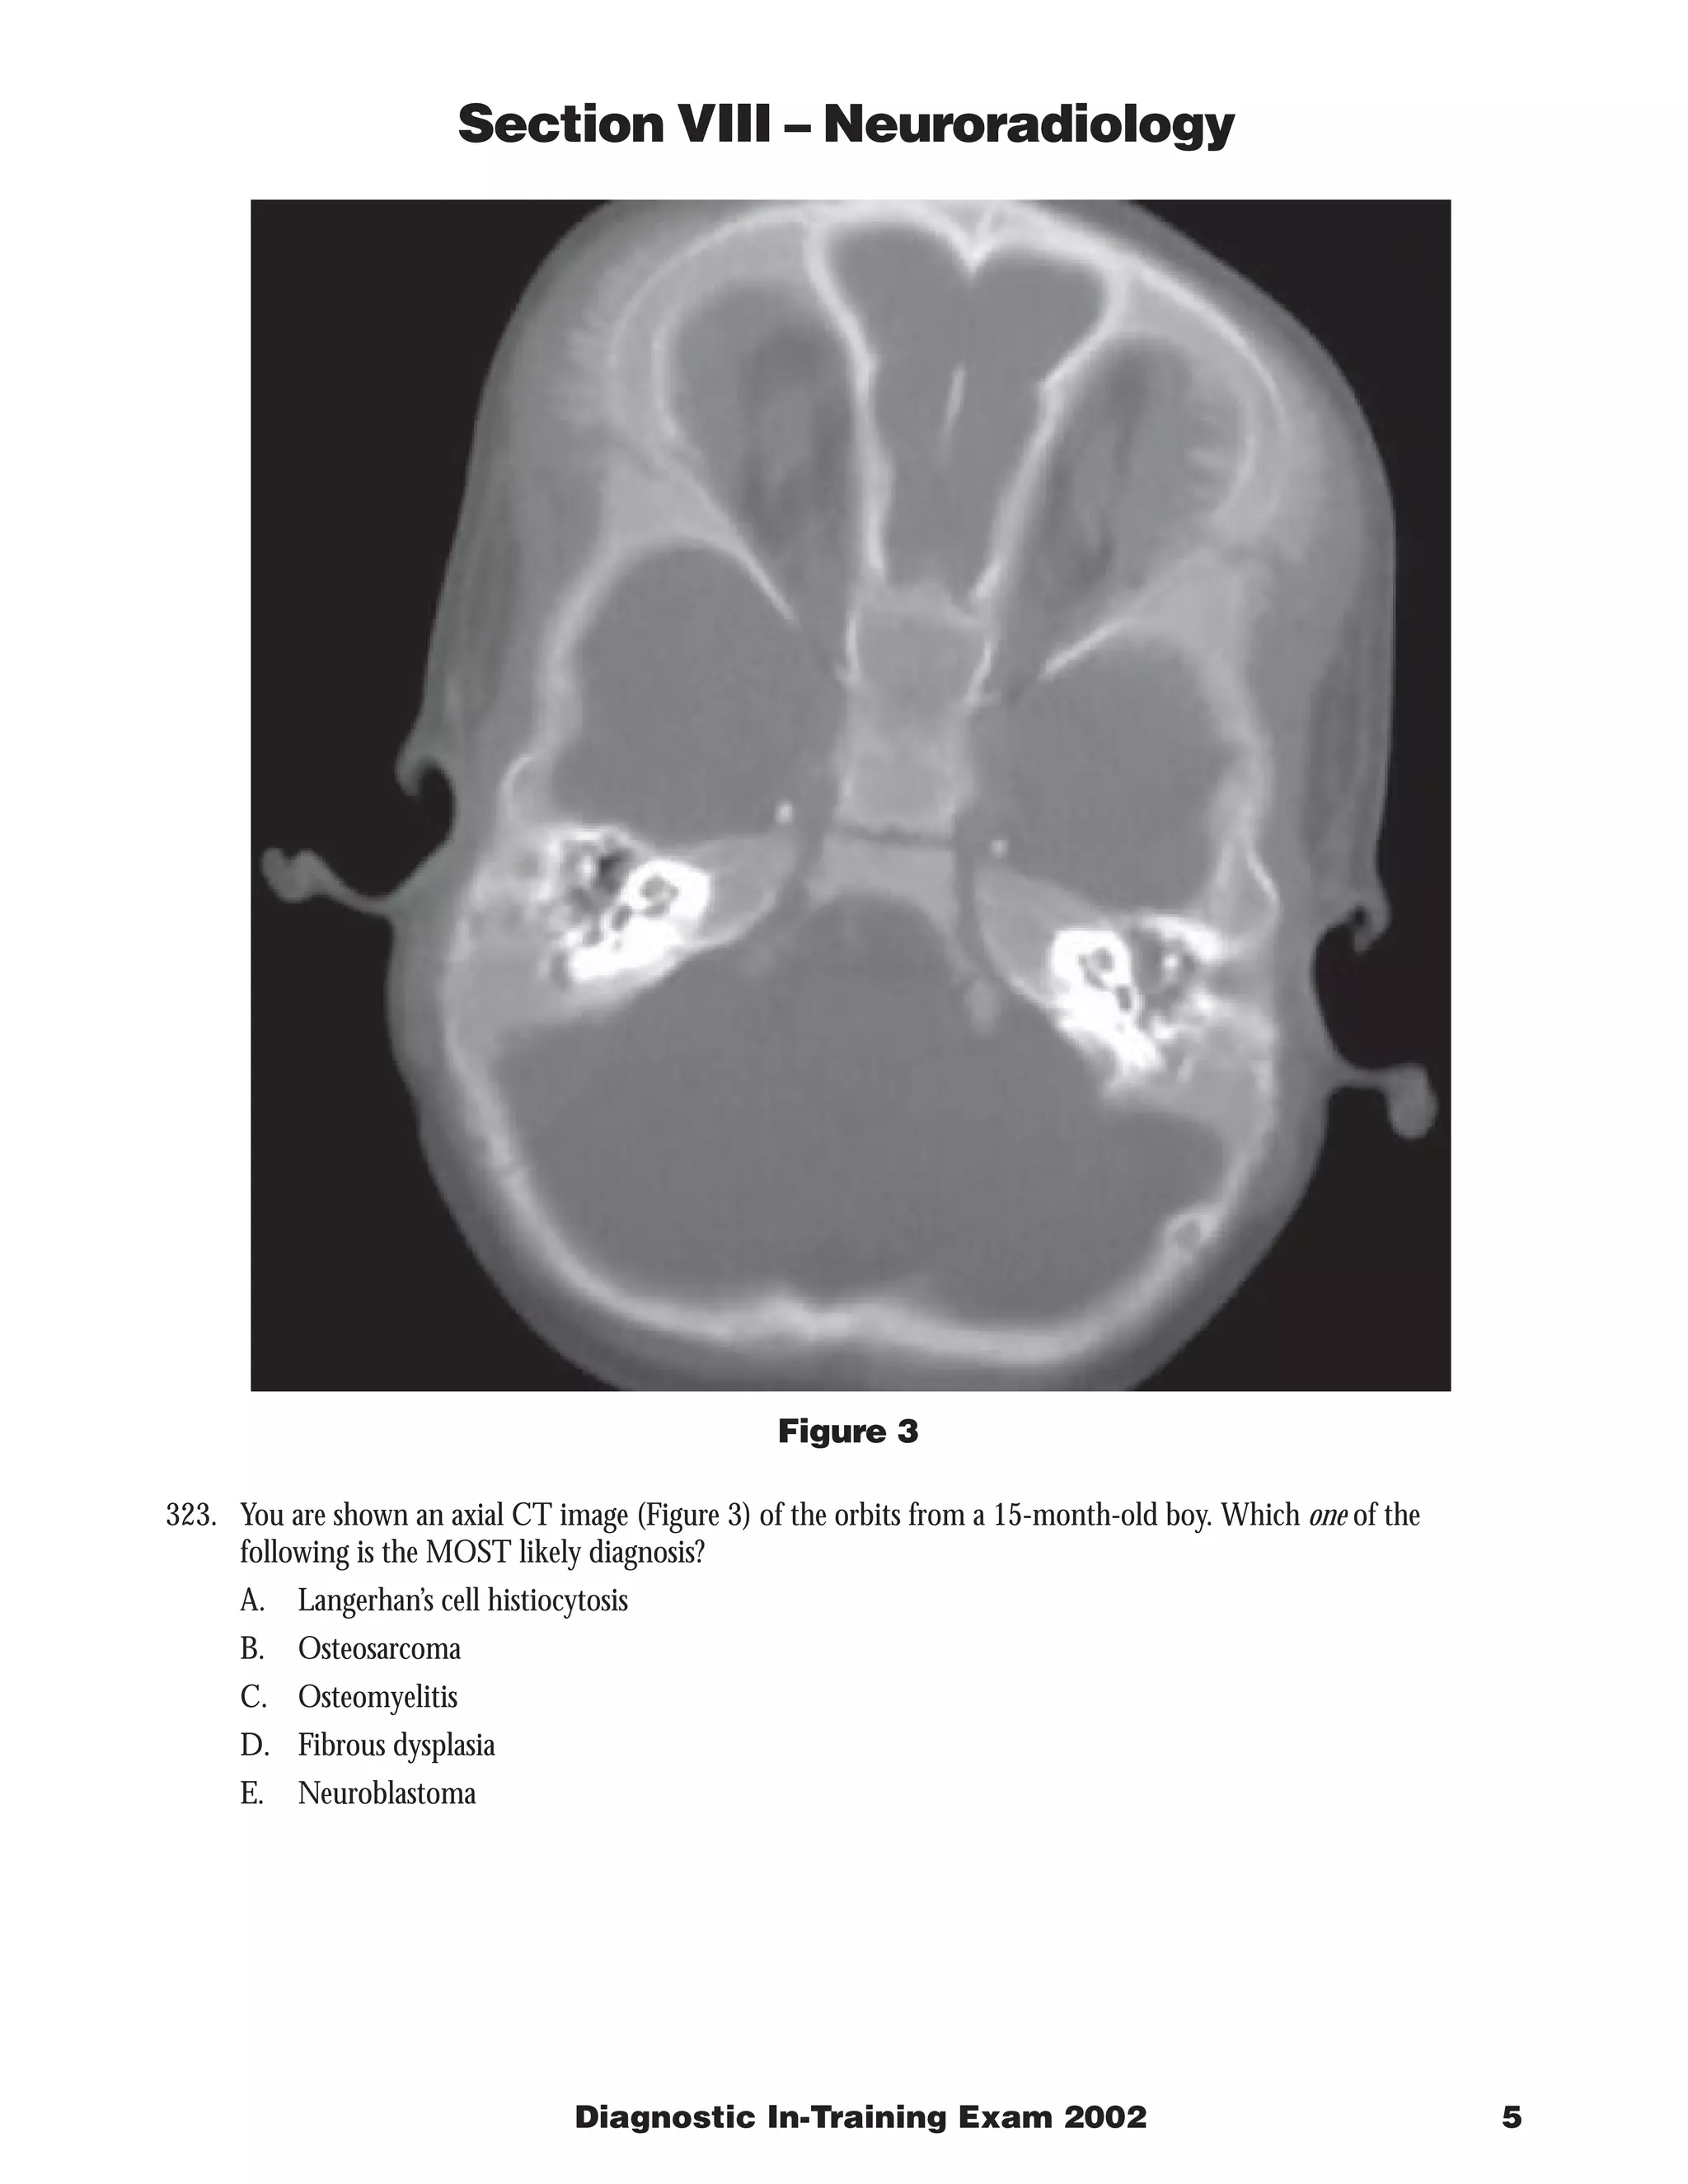

The document describes 3 radiology cases: 1) Images of the lumbar spine show a well-defined intradural mass at the filum terminale that is isointense on T1 and T2 with enhancement, most consistent with myxopapillary ependymoma. 2) Cerebral angiography shows a dural-based enhancing mass supplied by the external carotid artery, consistent with meningioma. 3) CT of the orbits in a 15-month-old boy shows spiculated bone formation in both orbits, suggestive of neuroblastoma metastases.